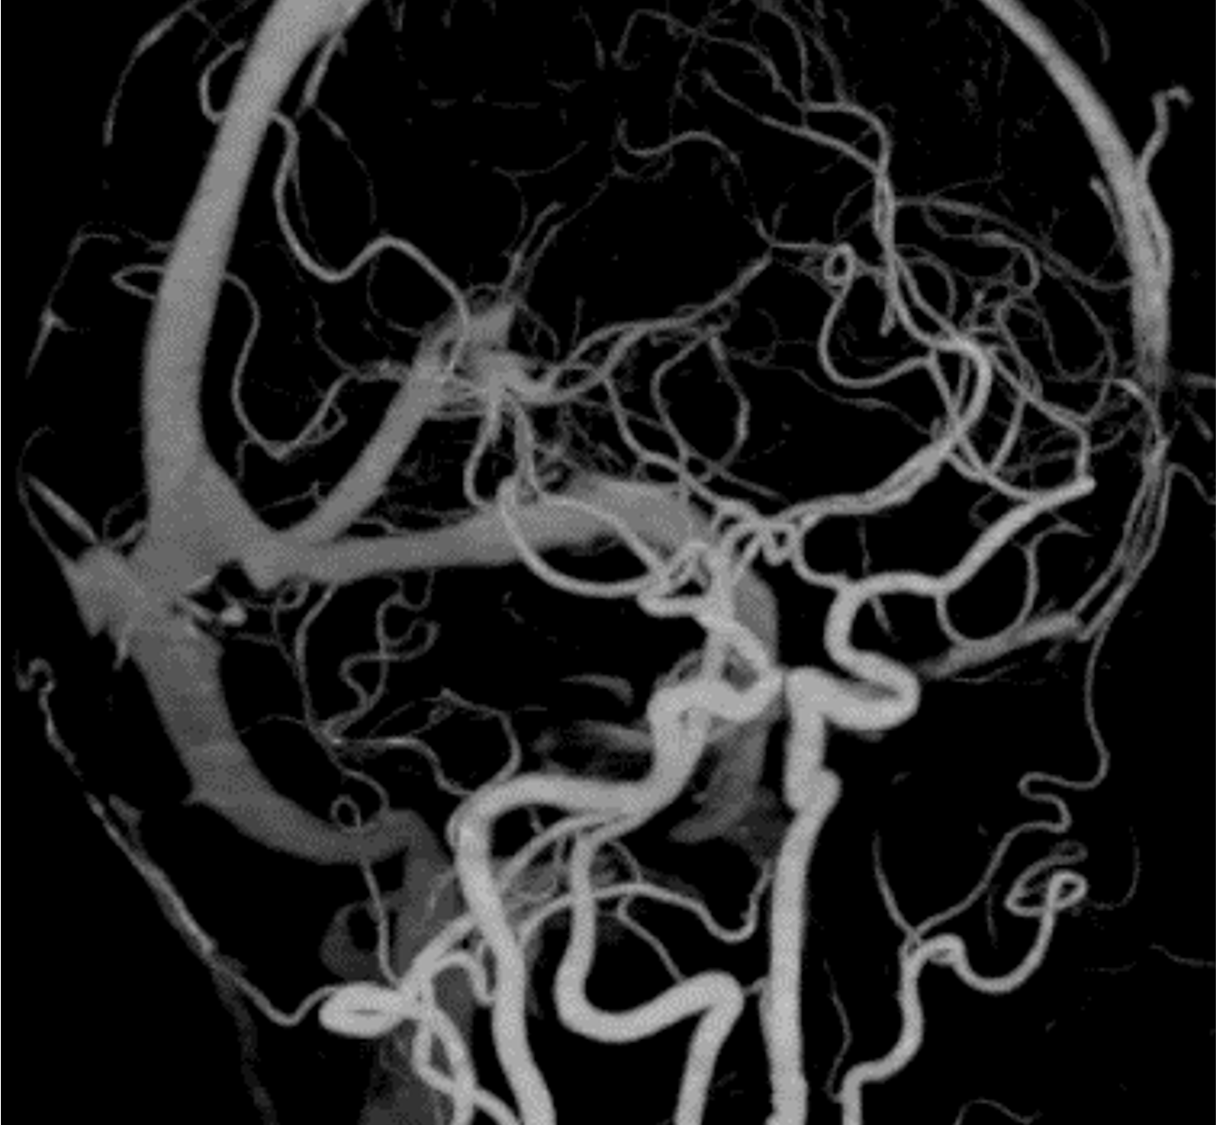

急性浸潤性真菌性副鼻腔炎は臨床経過が4週間以内と急速に進行する病態を示す。骨破壊を伴って副鼻腔から眼窩・海綿静脈洞・頭蓋内に浸潤が見られる。また血管侵襲性が強く、時に仮性動脈瘤形成や動脈狭窄・閉塞、血栓形成を引き起こす。血管に沿って進展し、骨破壊を伴わずに副鼻腔外に炎症が浸潤する場合がある。

造影CTでは骨破壊の有無、副鼻腔外への炎症浸潤、また仮性動脈瘤や動脈狭窄・閉塞、血栓形成を評価する。海綿静脈洞は動脈性病変、静脈洞血栓、炎症浸潤が混在する可能性があり、早期動脈相・後期動脈相・平衡相を撮像することでこれらを鑑別する。

静脈の関与が少ない早期動脈相で動脈を評価するため、ボーラストラッキング法を用いた撮像を行う。一般的には総頚動脈や内頚動脈、中大脳動脈にROIをおいてモニタリングされることが多いが、本症例では海綿静脈洞の描出ができるだけ少ないタイミングで行うために、大動脈弓部にROIを設定した。また、海綿静脈洞の評価の際、静脈の濃染があり、炎症性組織の濃染がないタイミングでの評価を行うため、静脈相ではなく後期動脈相を撮影している。平衡相での濃染の有無で炎症性組織と静脈洞内血栓の鑑別が可能である。